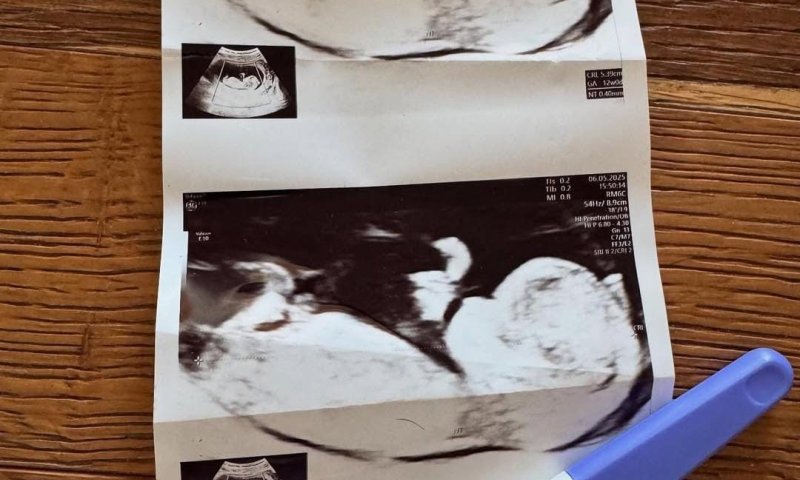

"אז אחרי הרבה מאמץ וזמן – הייתי בהריון", בישרה. "שבוע 14 כבר שבוע יחסית מתקדם שממש עוד שניה יודעים את מין העובר. אני מגיעה לבדיקה שגרתית ושלוש מילים שלא אשכח לעולם: 'מצטערת , אין דופק'".

המילים הללו, כפי שהיא מתארת, לא יישכחו לעולם. בתוך רגע, היא עברה ממצב של התרגשות והריון תקין למציאות קשה של מיון, הפלה, הרדמה וחדר ניתוח.